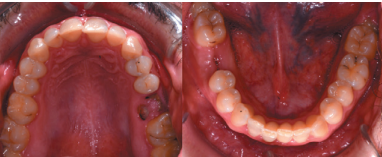

There were no medical-surgical antecedents of interest in his medical history, without known drug allergies or unhealthy habits. No relevant data was found on the extra oral examination. In the intraoral examination, non-restorable teeth were seen in the 2.6 and 4.6 position and the presence of retained lower third molars. (Figures 1 and 2).

The extraction of 4.6 and 2.6 and the curettage of the apical processes were planned, and the autotransplant of the left upper third molar (2.8) to sustain the 2.6 (Figure 5) was suggested to the patient.